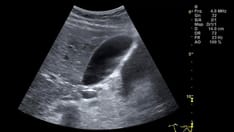

Ultrasonography with color Doppler analysis is the method of choice for the evaluation of adnexal torsion because it can show morphologic and physiologic changes in the ovary and can help determine whether blood flow is impaired. [9, 10, 11]

Video depicts 2 findings: (1) enlarged hypovascular left ovary and (2) flow in healthy right ovary. Small amount of intraperitoneal fluid surrounds left ovary.